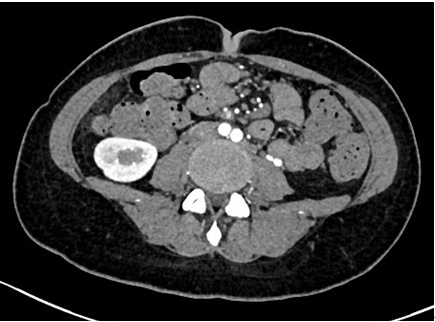

办好住院已经是1月13日下午四点了,介入科方淳主任及团队加班加点,当天晚上就为患者做了肠系膜动脉和静脉造影,结果没有发现大血管的问题,但是小血管充血、丰富,呈梳子样改变(称为“梳子征”,图1)。排除了肠系膜大血管的问题之后,高度怀疑肠系膜小血管炎可能,事不宜迟,赵家胜主任通过电话联系到风湿免疫科值夜班的王璇主治医生,王医生仔细询问了病史,了解到患者有过脱发和自发性流产的病史,结合本次肠道小血管炎的表现,高度怀疑系统性红斑狼疮引起的肠系膜血管炎。为了缓解患者的腹痛,挽救病人的生命,王璇医生基于对病情的判断,在化验结果尚未出来的情况下果断使用了糖皮质激素,第二天早上(1月14日)患者腹痛和恶心、呕吐即明显好转,患者胃口也开了,随后吃了点半流质,但下午又出现了腹痛和呕吐,这时化验结果也出来了(见图2),狼疮的标志性抗体-抗Sm抗体和ds-DNA抗体均阳性,证实了系统性红斑狼疮的诊断。赵主任和风湿免疫科汤建平主任共同查房后认为系统性红斑狼疮诊断明确,以急性腹痛起病,而且一发病就表现为狼疮危象的红斑狼疮少见,常规剂量激素疗效不佳,腹部CT结果显示肠壁水肿和胸腹水有进展(见图3、图4),需要立即进行大剂量激素冲击治疗。

第四天(1月16日)患者病情即明显好转,到1月24日复查CT,肠壁水肿消退(见图5)、胸腹水完全吸收(见图6),患者腹痛缓解,已能正常进食。